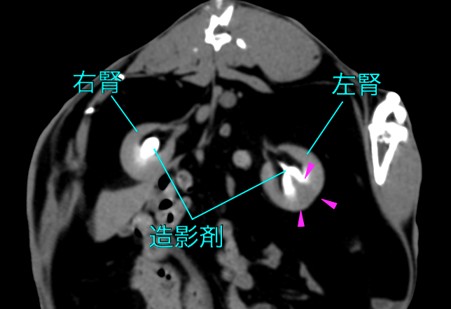

CT検査

CTでは腎臓のサイズを測定し、腫大や萎縮を評価できます。また、腎辺縁の不整や石灰化なども詳細に評価可能です 。CTはX線検査よりも高感度に石灰化を検出できる特徴があります 。初期の腎嚢胞、水腎症、腎盂の蓄膿も評価対象となります 。造影剤(ヨード製剤)を静脈内投与して行う造影CT検査は、腎臓の血流(灌流)と排泄機能の評価に用いられます。健康な腎臓では、造影剤投与後にまず皮質が強く濃染され(皮質期)、次いで髄質が濃染され(髄質期)、その後造影剤が腎盂へ排泄されます(排泄期) 。間質性腎炎や糸球体腎炎など、腎実質自体に障害がある場合、腎臓への血流や機能の低下により、この造影効果が全体的または部分的に低下します。実質が正常ほど濃染されない、または濃染までに時間がかかるといった所見が見られます。腎実質が斑状(まだら)に不均一に造影される場合は、線維化や炎症が不均一に存在することを示唆します 。造影CT検査は、腎梗塞の診断において非常に重要です 。急性期(発症から数日以内)の腎梗塞では、造影剤投与後の「動脈相」や「腎実質相」において、血流が途絶えた領域が特徴的な楔状の造影欠損域として描出されます。